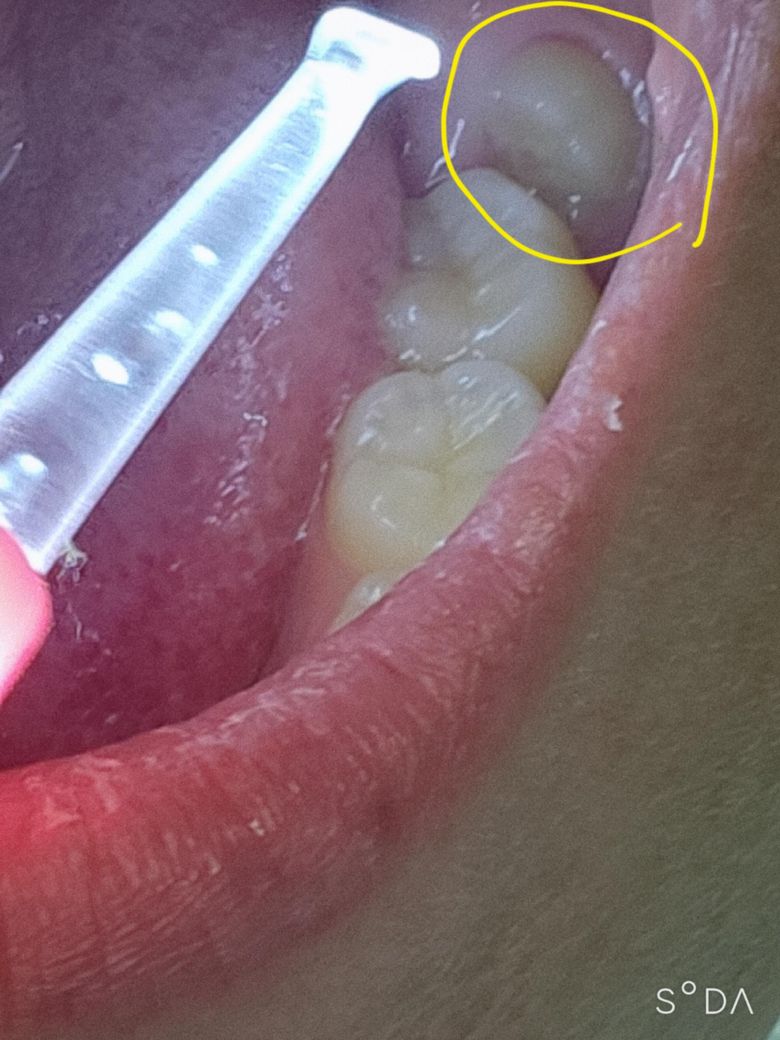

매복 사랑니 발치 수면마취 비용 얼마 들까요?

매복 사랑니 발치 할 때 수면마취 하고싶은데.. 이거 매복사랑니 뽑기 힘든 케이스인가요? 잇몸 째고 뽑아야 합니까..? 수면마취 보통 얼마정도 들까요..

잇몸 밖으로 많이 나와있기 때문에 수면마취 까지는 하지 않으셔도 될 듯 합니다. 금방 나올겁니다.

현재 사랑니가 매복되어 일부만 나와있는 경우 잇몸을 절개후 발치가 필요로 됩니다.

수면 마취의 경우 마취과 전문의가 있는 병원에서 가능하며 병원마다 금액차이가 있으나,10-30만원정도의 비용이 발생할수 있습니다.